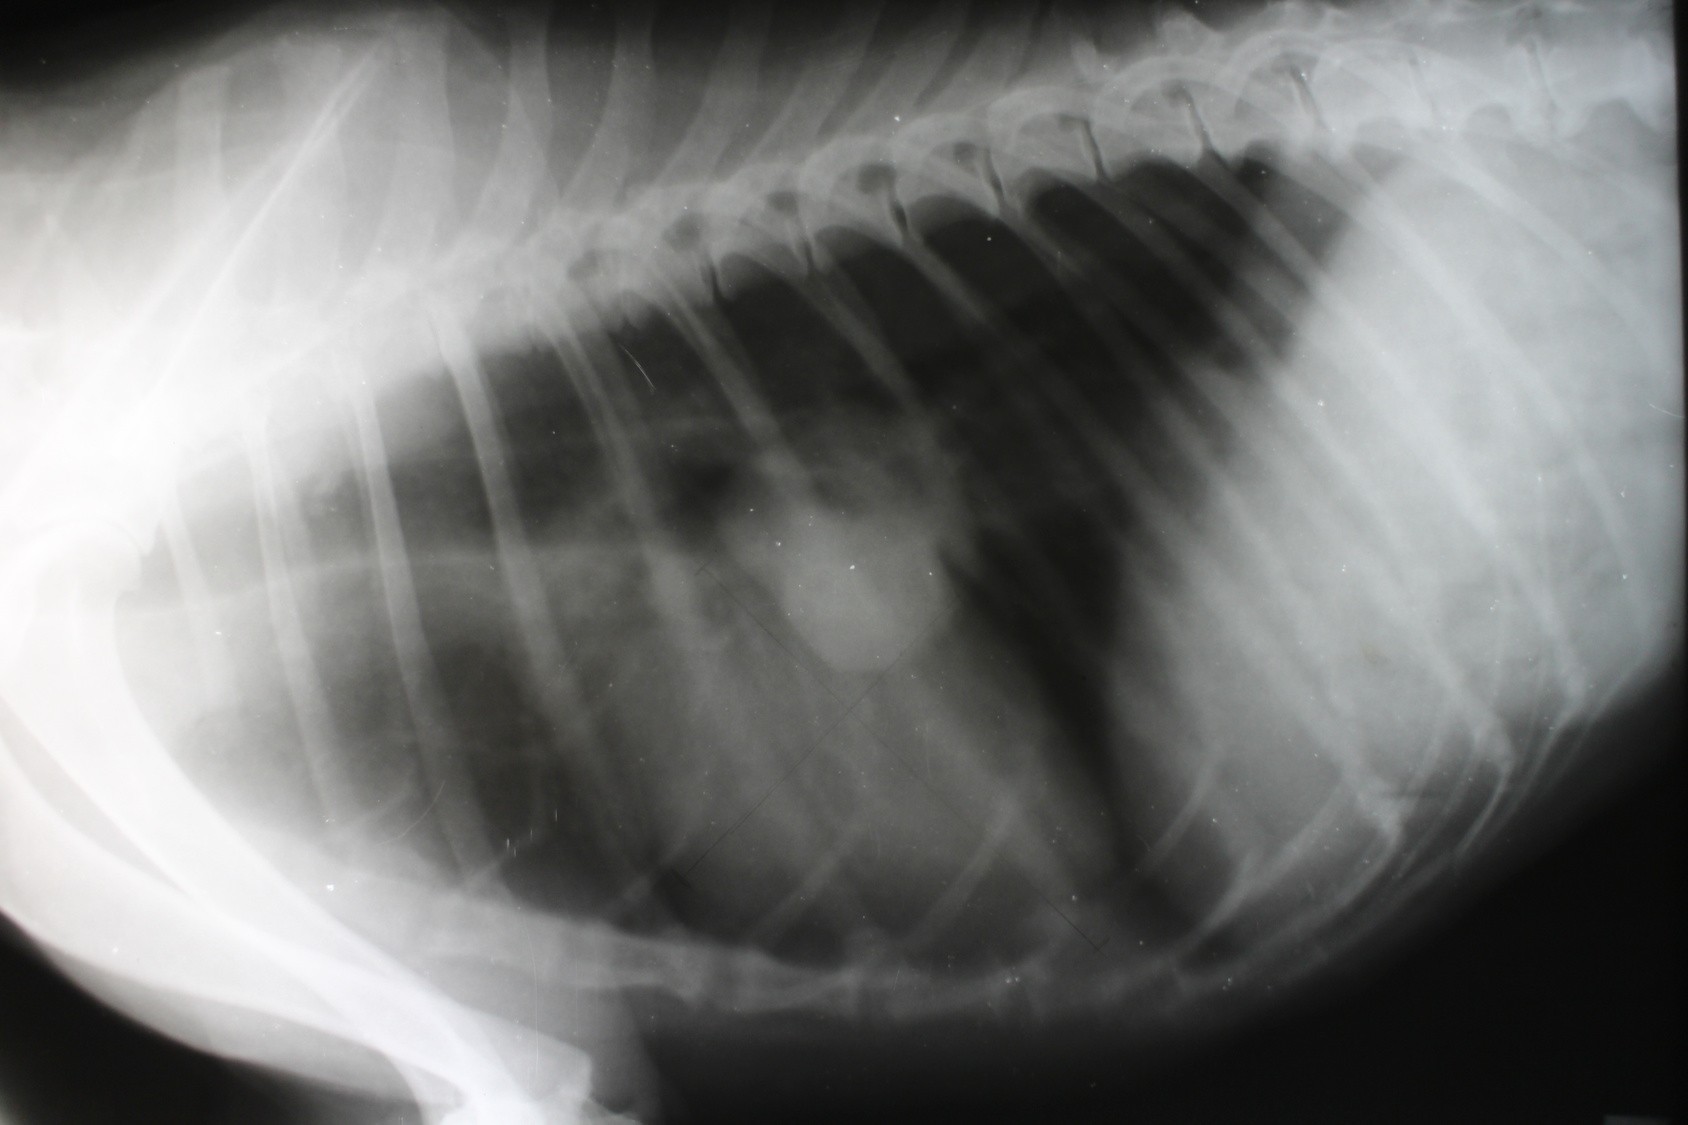

Carcinoma abscedado del pulmón estudio prospectivo. Hospital universitario «manuel fajardo» carcinoma abscedado del pulmón estudio prospectivo. Dr. Carlos a. Romero díaz, 1 dr. Juan c. Barrera ortega, 2 dr. Orestes n. Mederos curbelo, 3 dr. Jesús m. Valdés jiménez 4 y dr. Alexis cantero ronquillo 5 resumen. El carcinoma abscedado del pulmón es un problema serio y complejo en el que la solución es controvertida. Metástasis pulmonar síntomas y complicaciones. Metástasis al pulmón medlineplus enciclopedia médica. Conozca más sobre la politica editorial, el proceso editorial y la poliza de privacidad de a.D.A.M. A.D.A.M. Es también uno de los miembros fundadores de la junta Ética de salud en internet (health internet ethics, o hiethics) y cumple con los principios de la fundación de salud en la red (health on the net foundation hon.Ch). Sntomas fsicos en los ltimos dos a tres meses de vida. Puede que algunas personas descubran un temor al dormir por miedo a que ya no vayan a despertar. Esto es un temor natural y muy real. El necesitar ms tiempo para dormir es normal durante los ltimos meses de vida. El distanciamiento de las personas, el retraerse y concentrarse en s mismo(a) y hablar menos tambin es comn en estos momentos.